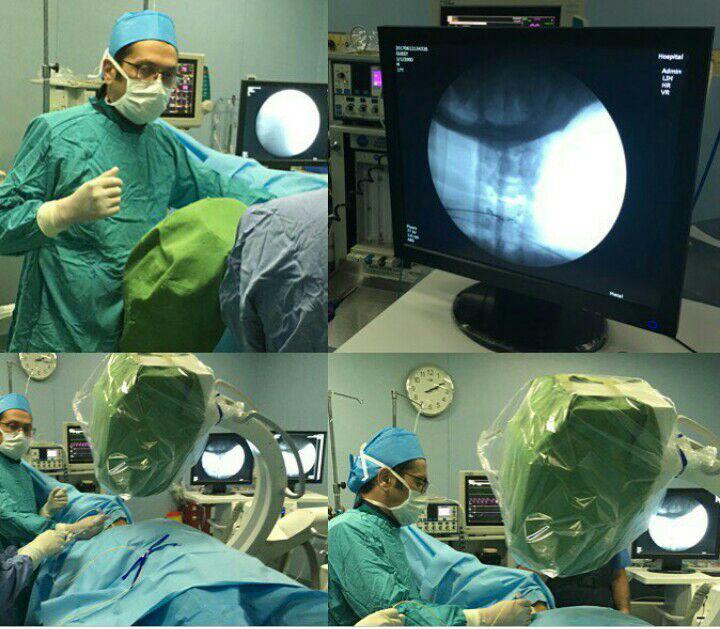

-لیزر(جراحی بسته) دیسک کمری

-اوزون تراپی دیسک بین مهره ای

-درمان تنگی کانال نخاعی غیرقابل جراحی

استفاده از روشهایی مانند تزریقات تخصصی (مانند اپیدورال، بلوک عصبی)، طب سوزنی، فیزیوتراپی، تحریک الکتریکی عصب و روشهای کم تهاجمی جراحی.